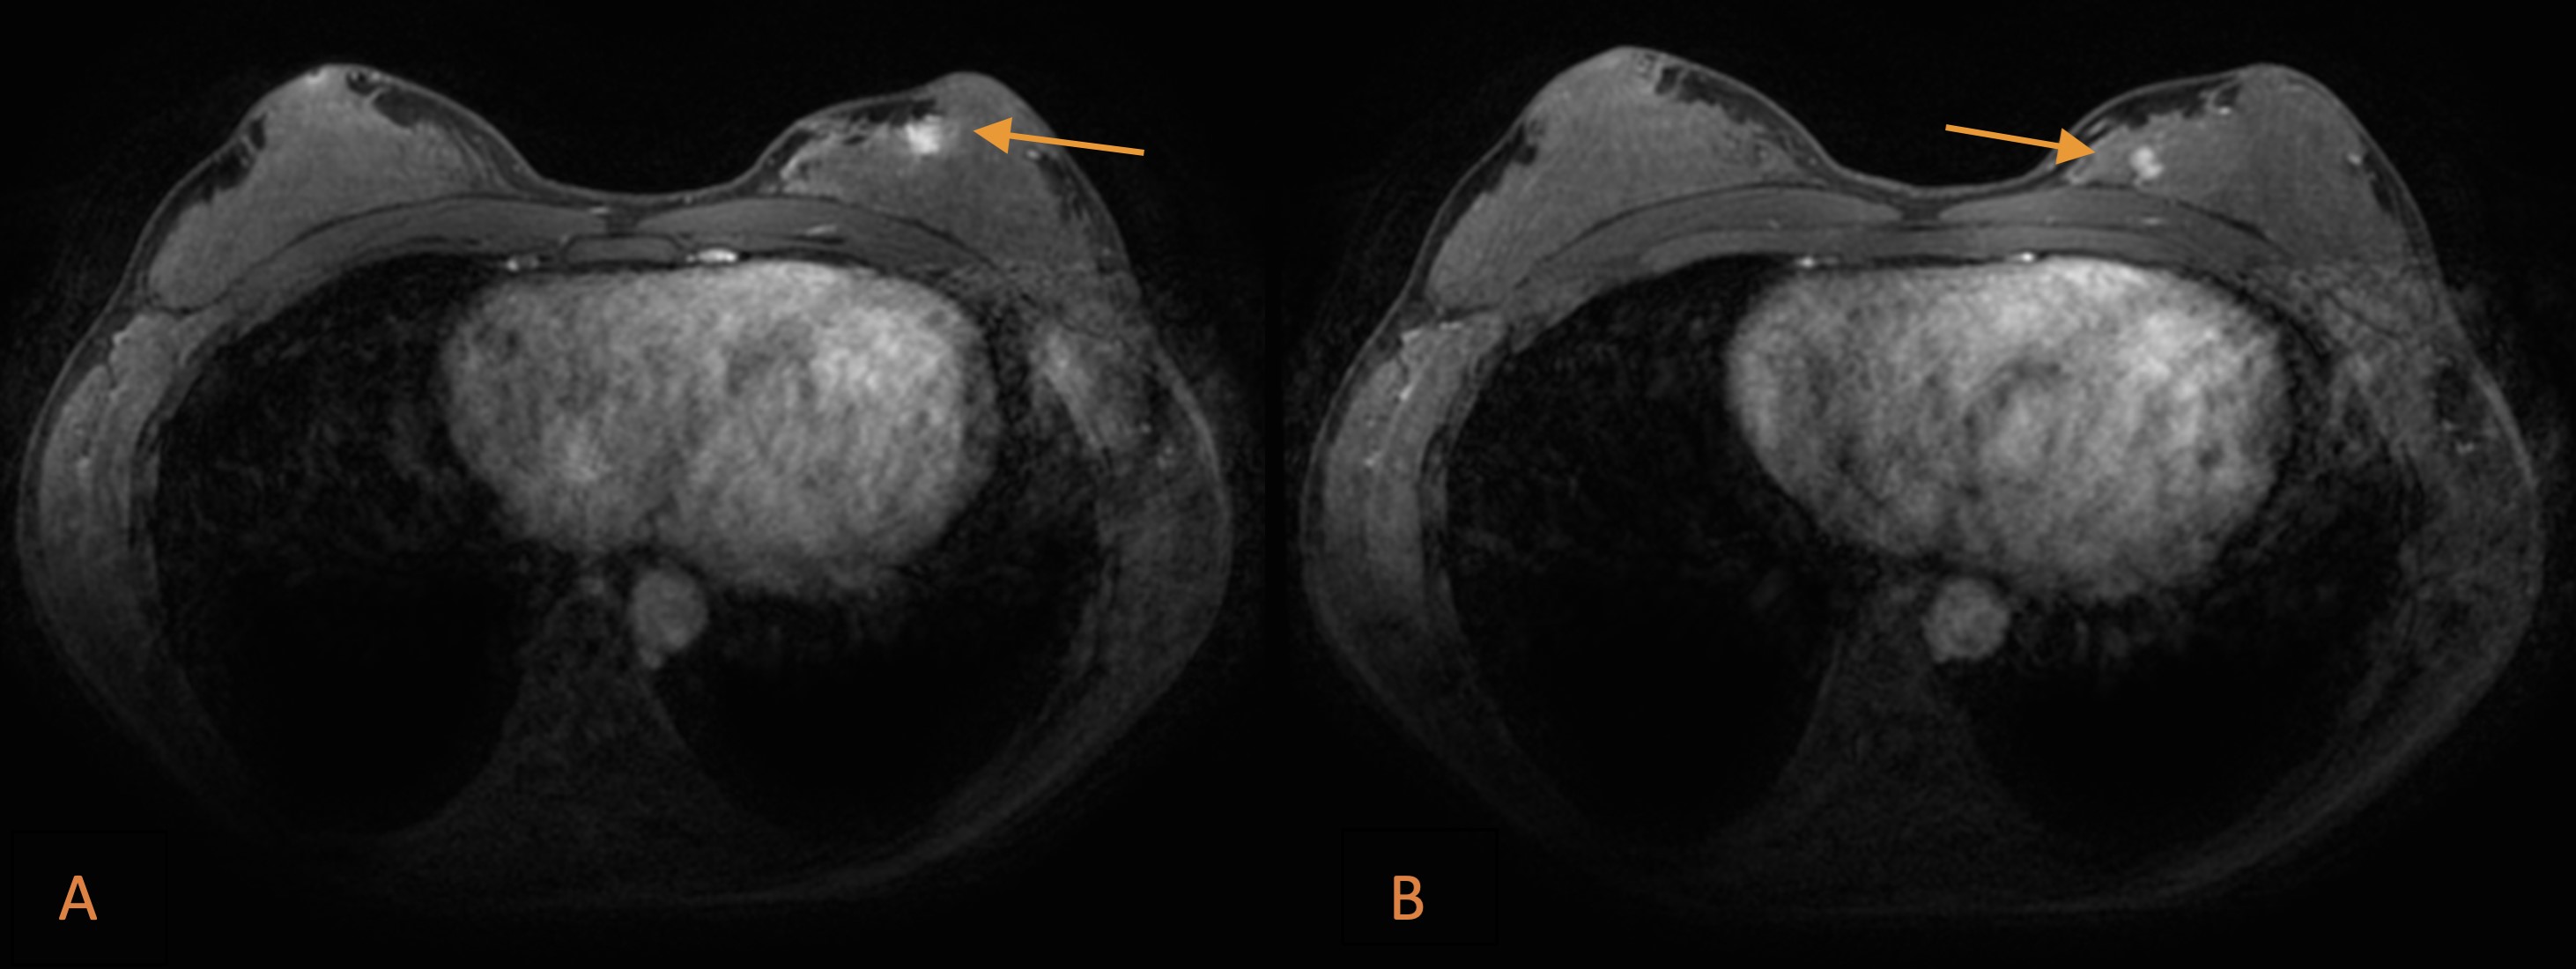

Contrast-enhanced breast MRI (3T) revealed the infracentimetric, enhancing lesion in the periareolar region at the transition of the left inner quadrants, initially detected on ultrasound. An additional 6 mm nodular lesion with similar enhancing pattern, located about 11 mm posteriorly and medially, in the same breast quadrant was found (Fig. 2).

Figure 2: Breast MRI: T1-weighted fat-suppressed, contrast-enhanced sequences revealing the infracentimetric lesion initially detected by ultrasound, enhancing in the periareolar region (arrow in A). An additional 6 mm nodular lesion in the same breast quadrant was detected (arrow in B).